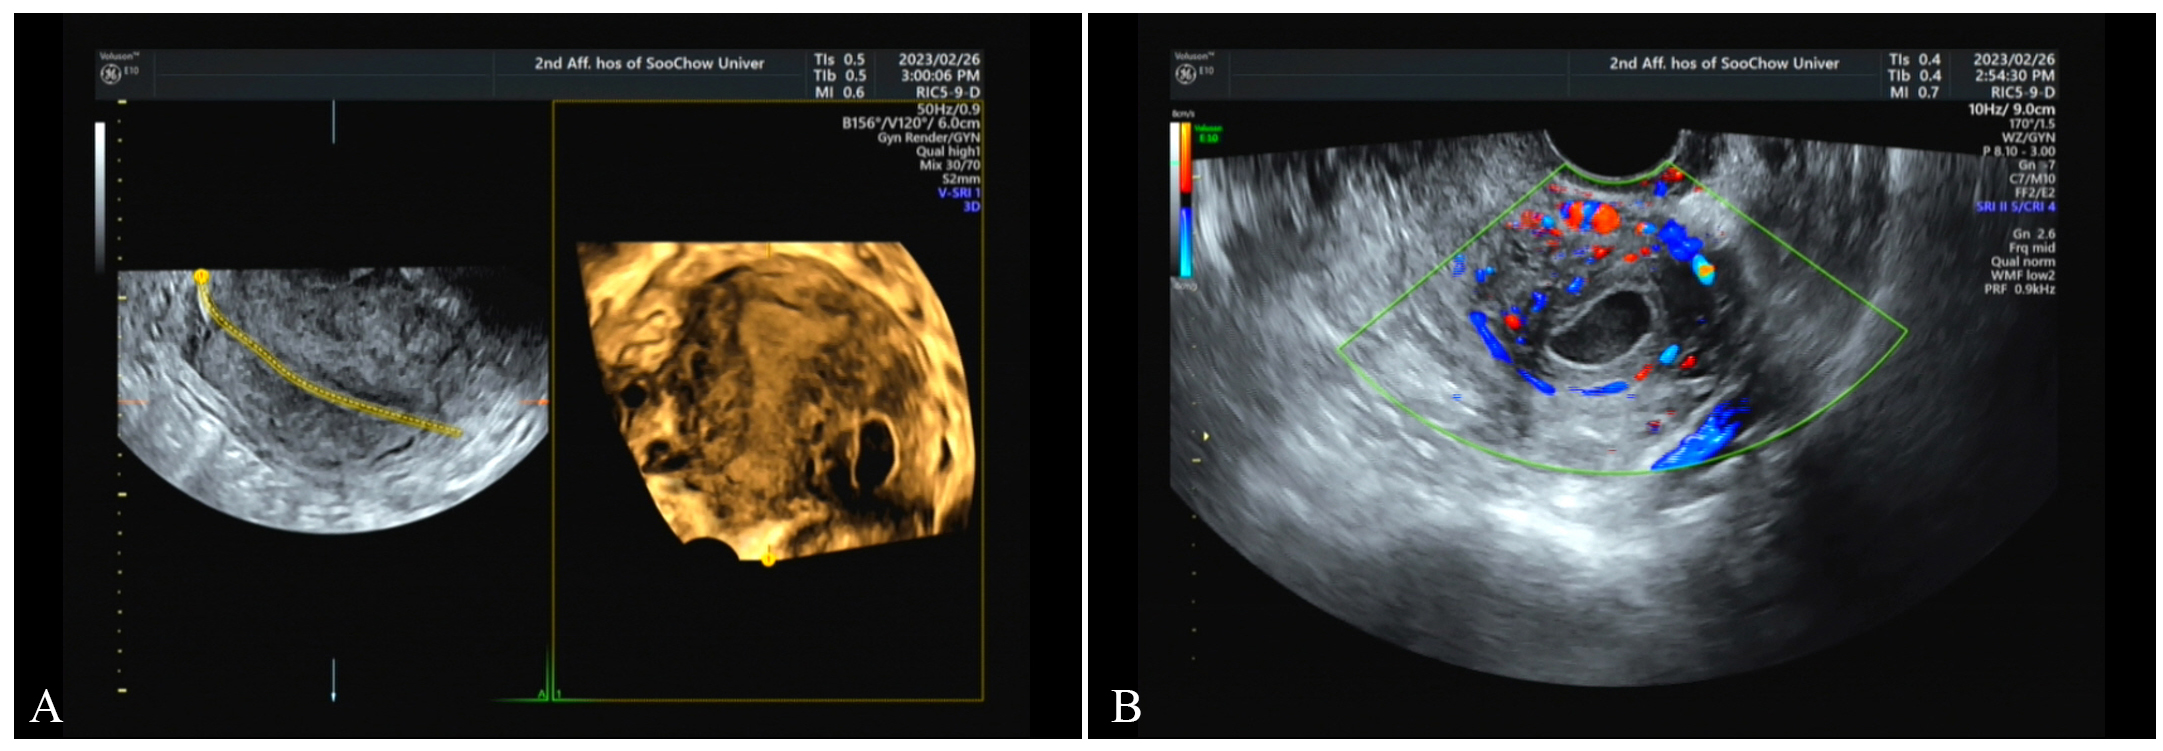

Fig. 3. March 1, transvaginal ultrasound scan. (A) The mass has enlarged compared with previous findings. (B) The surrounding blood flow signals have increased.